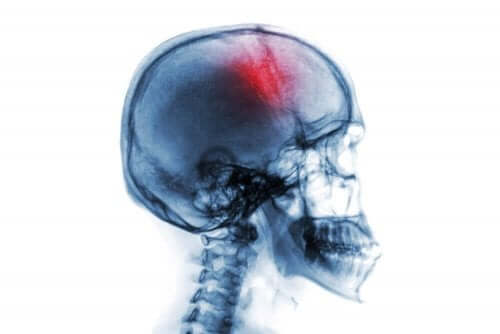

İnme, birçok risk faktörü ve belirti ile birlikte gelen ani bir nörolojik hastalık durumudur. Beyindeki kanama veya kan dolaşımı kaybını ifade eder.

Kan akışı beyne düzgün bir şekilde ulaşmazsa, beyin dokusunun ölümü meydana gelir. Bu nedenle de, sakatlığa ve hatta ölüme yol açabilecek nörolojik bir eksiklik oluşur.

- “Ictus” veya “İnme.” Bu beyindeki kan akışının kesilmesini gerektirir. İlk olarak, beyni besleyen kan damarlarının herhangi birinde (iskemi) bir engel olabilir. Bu genellikle ateroskleroz problemleri ile ilişkilidir. İkinci olarak, intraserebral kanama veya bir hemorajik felce bağlı olabilir.